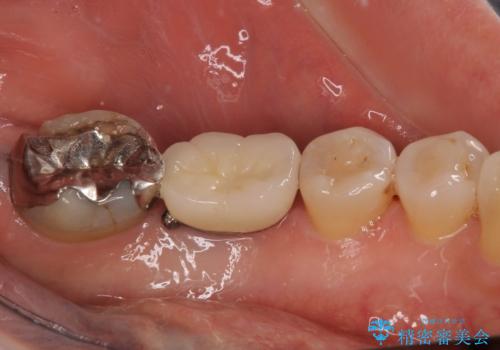

- 銀歯の装着されている奥歯がしみるとのことで来院された患者様です。

銀歯周辺の歯が欠けており、むし歯も進行している状態であったので、オールセラミッククラウンにて補綴治療を行うこととしました。